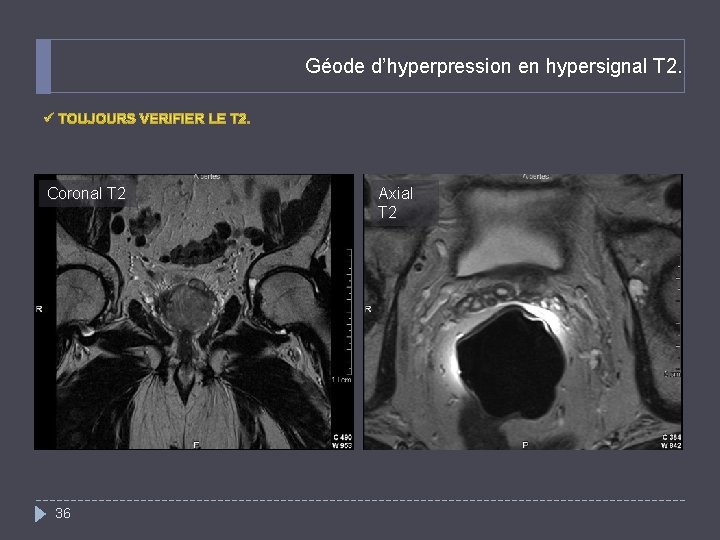

Quel est votre diagnostic? Patient suivi pour un cancer de la prostate métastatique. Découverte d’une lésion en hyposignal de la branche ilio pubienne gauche (flèche) Axial T 1 35 Axial Diffusion, b=800 (même niveau que T 1)

Géode d’hyperpression en hypersignal T 2. Coronal T 2 36 Axial T 2